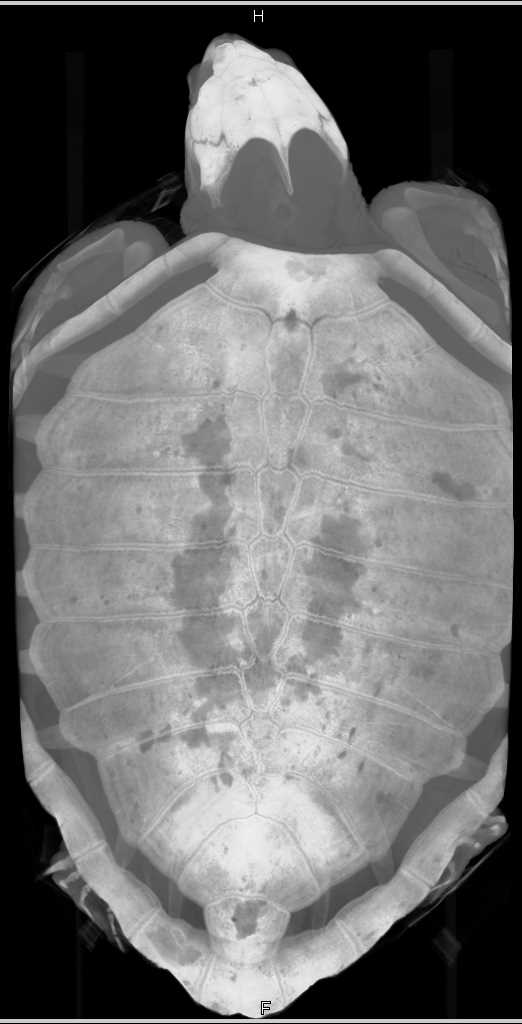

Turtle Lungs with Bronchial Tree